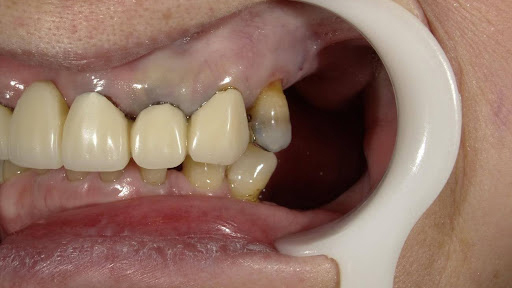

After

枚方市のインプラントの症例

M・I 様 女性 70代

症状としては、左下56は、歯周病で欠損したと考えられるが、かなりの骨欠損をともなっていた。左上456に関しては、動揺が大きく、炎症が起き、排膿、および、歯性上顎洞炎を起こしていた。

治療法としては、動揺がひどくなってきて、炎症の症状もあったため、左上56の抜歯を希望。インプラント治療をその後、希望したため、左上4に関しては抜歯即時埋入。左上6に関しては、既存骨1から2mmでインプラント治療が厳しい状態であったが、グラフトレスサイナスリフトを行い、治療期間5か月はかかるということを説明して、インプラント埋入をおこないました。その後、2か月半後、大幅に骨が欠損している下顎56に対して、ショートインプラントを使用して、下顎神経の損傷を避けて、インプラント埋入を終えています。その後2か月後に光学印象で印象を行い、上顎刺億456歯、3ユニットのジルコニアブリッジを装着。下顎左側56に関しては、骨欠損が大きいため、歯冠長がだいぶ長くなるため、ジルコニアの連結冠を装着して治療を終えた。

治療結果は、上顎6に関しては、既存骨が少なく、厳しい治療ではありましたが、5か月で治療を終え、患者様の負担を最小限に抑えるができたと考えます。(従来のサイナスリフトでは、このようなケースでは1年以上、1年程度の治療期間がかかるか、治療が不可能と言われるケースだと考えます。)また、下顎は骨欠損が大きく、下歯槽管のリスクが起きることが考えられますが、ショートインプラントを使用することで安全に治療を行うことができました。

治療の期間・回数:治療期間5か月(上顎456 3ピースブリッジの治療は5か月(上顎既存骨が2mm程度しかなく、骨結合に時間がかかるケースであったために、5か月の治療期間が必要であった。)(左下56に関しては2か月半で治療を終えています。)治療回数は、13回。

治療の価格:1,474,000円(税込)

治療費の内訳:左上46および左下56のインプラント基本料(フィックスチャー及び手術費用、投薬費用、レントゲン費用、インプラント上部費用(アバットメントおよびジルコニアクラウンの費用用)330000円(税込み)×4本分 1320000円(税込)。左上5ジルコニアポンテック費用88000円(税込)。オプション費用、左上4抜歯即時埋入加算(人工骨費用を含む)+グラフトレスサイナスリフト費用 33000円(税込)、左上6グラフトレスサイナスリフト費用 33000円(税込)

治療のリスクや副作用:手術後に、痛みや腫れ、出血、合併症などを引き起こす可能性があります。噛む感覚がご自身の歯と異なる場合があります。見た目がご自身の歯と異なる場合があります。手術後にメインテナンスを継続しないと、インプラントが抜け落ちる可能性があります。